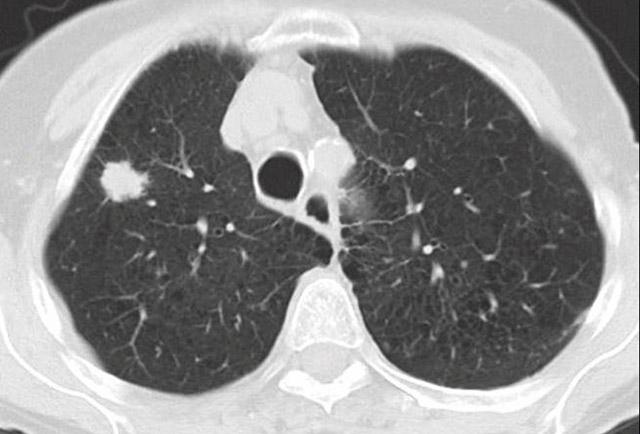

CT and PET scans both have false positives and negatives, he said. So if physicians rely on imaging alone, the cancer's stage, or determination of whether the disease has spread, might be classified incorrectly. That misclassification can inadvertently result int providing patients with either the wrong or less-than-optimal treatments, he said.